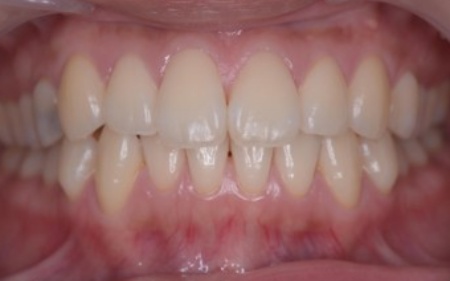

10代女性 乱れた歯並びと噛み合わせをワイヤー矯正で改善した症例

「歯並びが悪い。とくに八重歯が気になる」とご相談いただきました。

拝見したところ、上下の前歯を中心に、歯が正常な位置からずれたりねじれたりしてデコボコに生えている状態でした。

矯正治療終了後は、歯が元の位置に戻ろうとする後戻りを起こすリスクがありますが、治療後15年たった現在も後戻りすることなく、正しい歯並びを維持しています。